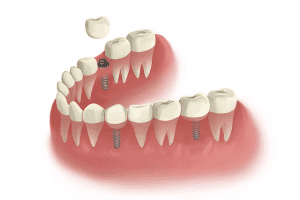

Implant Retained Bridge

When there are several missing teeth, dental implants may be used to offer support to a implant retained bridge. An implant retained bridge can replace up to 6 teeth in a row using just 2 supporting implants.

This solution is more affordable than placing an individual implant for each missing tooth, and once in position the bridge will look like a row of natural teeth. Unlike conventional dental bridges, an implant supported bridge does not require support from surrounding teeth, because the roots of lost teeth are replaced.

Implant Retained Bridge

When there are several missing teeth, dental implants may be used to offer support to a implant retained bridge. An implant retained bridge can replace up to 6 teeth in a row using just 2 supporting implants.

This solution is more affordable than placing an individual implant for each missing tooth, and once in position the bridge will look like a row of natural teeth. Unlike conventional dental bridges, an implant supported bridge does not require support from surrounding teeth, because the roots of lost teeth are replaced.